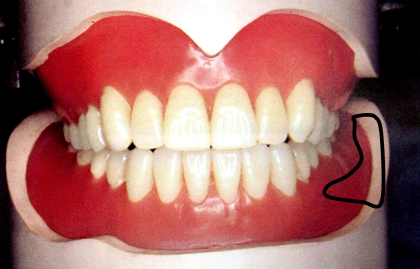

临床上,根据无牙颌每个解剖部位的不同特点,全口义齿制作时都要做相应的特殊处理,这与全口义齿的固位、稳定、美观、功能等都息息相关。

无牙颌的分区:

①主承托区:垂直于颌力受力方向的区域。包括牙槽嵴顶、腭部穹隆区、颊棚区等,该区不易出现骨吸收,能承担咀嚼压力。

②副承托区:与牙合力受力方向成角度的区域。包括上下颌牙槽嵴顶的唇、颊和舌腭侧(不包括硬区),与颊舌的界限在粘膜和口腔前庭黏膜反折线,支持能力较差,不能承受较大压力,只协助主承托区承受咀嚼压力。

③边缘封闭区:义齿边缘接触的软组织部分,如黏膜皱襞、系带附着部、上颌后堤区和下颌磨牙后垫。

此区有大量疏松结缔组织,与义齿边缘紧密贴合,防止空气进入基托与组织之间,产生良好的边缘封闭作用,从而形成负压和吸附力保证义齿固位。

④缓冲区:无牙颌上的颧突、上颌结节的颊侧、切牙乳突、下颌隆突、颌舌骨嵴,牙槽嵴上的骨尖、骨棱等部位。这些部位粘膜较薄,基托相应部位应磨除少许做缓冲处理。

⑤后堤区: 腭小凹后方,轻压颤动线以获得良好的封闭。